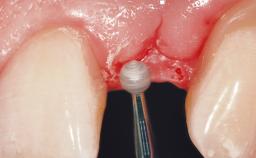

Immediate Flapless Placement of an Implant in a Maxillary Left Central Incisor Site

A 42-year-old female patient was referred to our clinic at the School of Dentistry of the University of São Paulo in November 2004, presenting a deficient restoration in the upper left central incisor. The clinical examination revealed no gingival retraction or any signs of gingival inflammation and, therefore, previous periodontal treatment was not considered. The patient presented a high lip line at full smile and a thin tissue biotype. This combination characterized a high-risk situation from an anatomic point of view, which required careful preoperative planning and cautious surgical execution.

Placement Protocol Immediate implant placement

Tooth Site Maxillary incisor or canine

Socket Morphology Single-root socket

Socket Integrity Sufficient, with intact bone walls